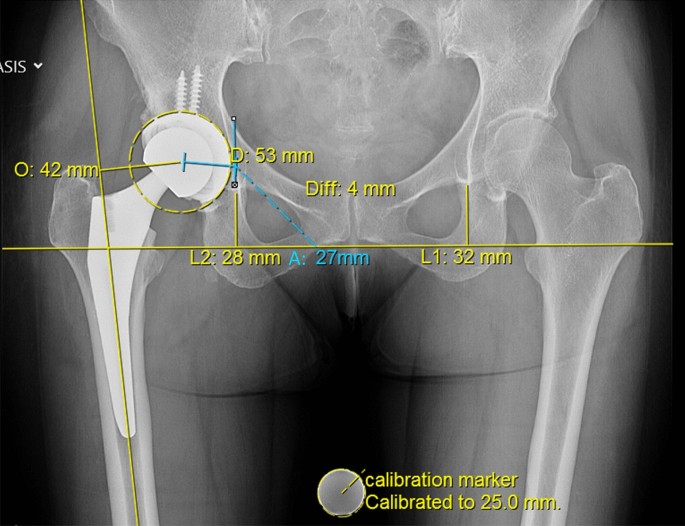

To calculate leg length (LL) the Ranawat technique was used10,17,18 (Fig. 1). The trans teardrop line was defined as the standard line. The perpendicular distance from this horizontal line to the apex of the lesser trochanter was measured and displayed in the Picture Archiving Communications System PACS templating system. The difference in between the affected und the contralateral unaffected hip was termed hip length discrepancy (HLD), which was determined in each patient pre- and postoperatively.

Leg length (LL) was measured with the Ranawat technique and hip offset (OS) was calculated as the sum of femoral and acetabular offset. Analysis of radiologic images concentrated on the discrepancy in leg length (LLD) and hip offset (OSD) between the affected and unaffected hip. (O: femoral offset, A: acetabular offset, Diff: LLD).

Hip offset (OS) was calculated as the sum of femoral and acetabular offsets10 Fig. 1). Femoral offset was defined as the perpendicular distance from the center of rotation of the femoral head to the line of action of the abductor muscles. Acetabular offset is the perpendicular distance from the center of rotation of the femoral head to the vertical trans-teardrop line. The difference in OS between the affected und the contralateral unaffected hip was termed offset discrepancy (OSD), which was determined in each patient pre- and postoperatively.